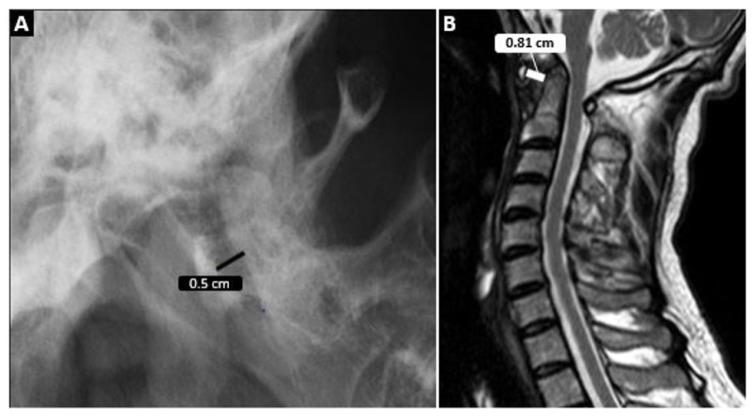

In this retrospective analysis, cervical CT or MRIs of patients with RA, SpA, or PsA, taken for any reason between 2010 and 2020, according to ICD-10 codes, were scanned. Demographic data of the patients were recorded. CCJ involvements (atlantoaxial, vertical, or subaxial subluxation, odontoid process involvement) were reevaluated by an experienced radiologist. The control group consisted of consecutive patients without inflammatory arthritis.

Exactly 459 patients (204 RA, 200 SpA, and 55 PsA) and 78 patients in the control group were included in the study. CCJ involvement was detected in 101 (49.5%) RA, 53 (26.5%) SpA, 10 (18.2%) PsA, and 4 patients (5.1%) in the control group (p < 0.001). The odontoid process was one of the main targets, especially in RA patients (69 (33.8%)), which was significantly higher than in the SpA, PsA, and control groups. Although vertical subluxation (VS) was numerically higher in the RA and SpA groups compared to the control group, VS-related brainstem compression was relatively uncommon: 6 (2.9%) in RA, 1 (0.5%) in AS, and none in the PsA and control groups.

在这项回顾性分析中,根据 ICD-10 编码,扫描了 2010 年至 2020 年间因任何原因接受 RA、SpA 或 PsA 颈椎 CT 或 MRI 的患者。记录患者的人口统计学数据。由一位有经验的放射科医生重新评估 CCJ 受累(寰枢关节、垂直或下颈椎半脱位、齿状突受累)。对照组由连续无炎性关节炎的患者组成。

共纳入 459 例患者(204 例 RA、200 例 SpA 和 55 例 PsA)和 78 例对照组患者。RA、SpA、PsA 和对照组患者中分别有 101 例(49.5%)、53 例(26.5%)、10 例(18.2%)和 4 例(5.1%)存在 CCJ 受累(p < 0.001)。齿状突是主要的受累部位之一,尤其是在 RA 患者中(69 例,33.8%),明显高于 SpA、PsA 和对照组。虽然 RA 和 SpA 组的垂直半脱位(VS)数值高于对照组,但 VS 相关的脑干压迫相对少见:RA 组 6 例(2.9%),AS 组 1 例(0.5%),PsA 和对照组均无。